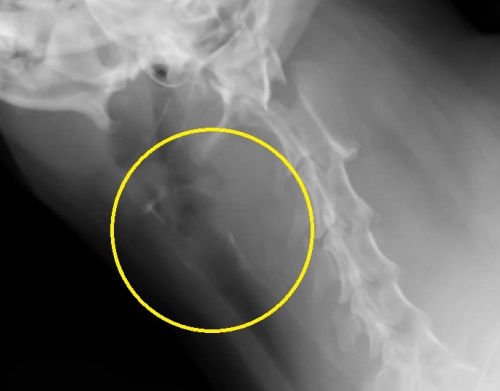

”ジャーキーを食べた直後”ということと、診察室での様子からやはり食道の異物が疑い、頸部のレントゲン検査に加えて、確定診断のためにバリウムによる食道造影を実施したのが下写真です。

頸部レントゲンで、「異物が存在する」はずの黄色の丸で囲んだエリアには異常は認められません。

ここでバリウム造影検査を行ったものが下写真です。上の写真黄色のサークル内でほぼ見えない異物が造影剤で浮かび上がっているのがお分かりだと思います。異物は咽頭のすぐ下から食道に入って数センチ以内の場所に存在しているようです。